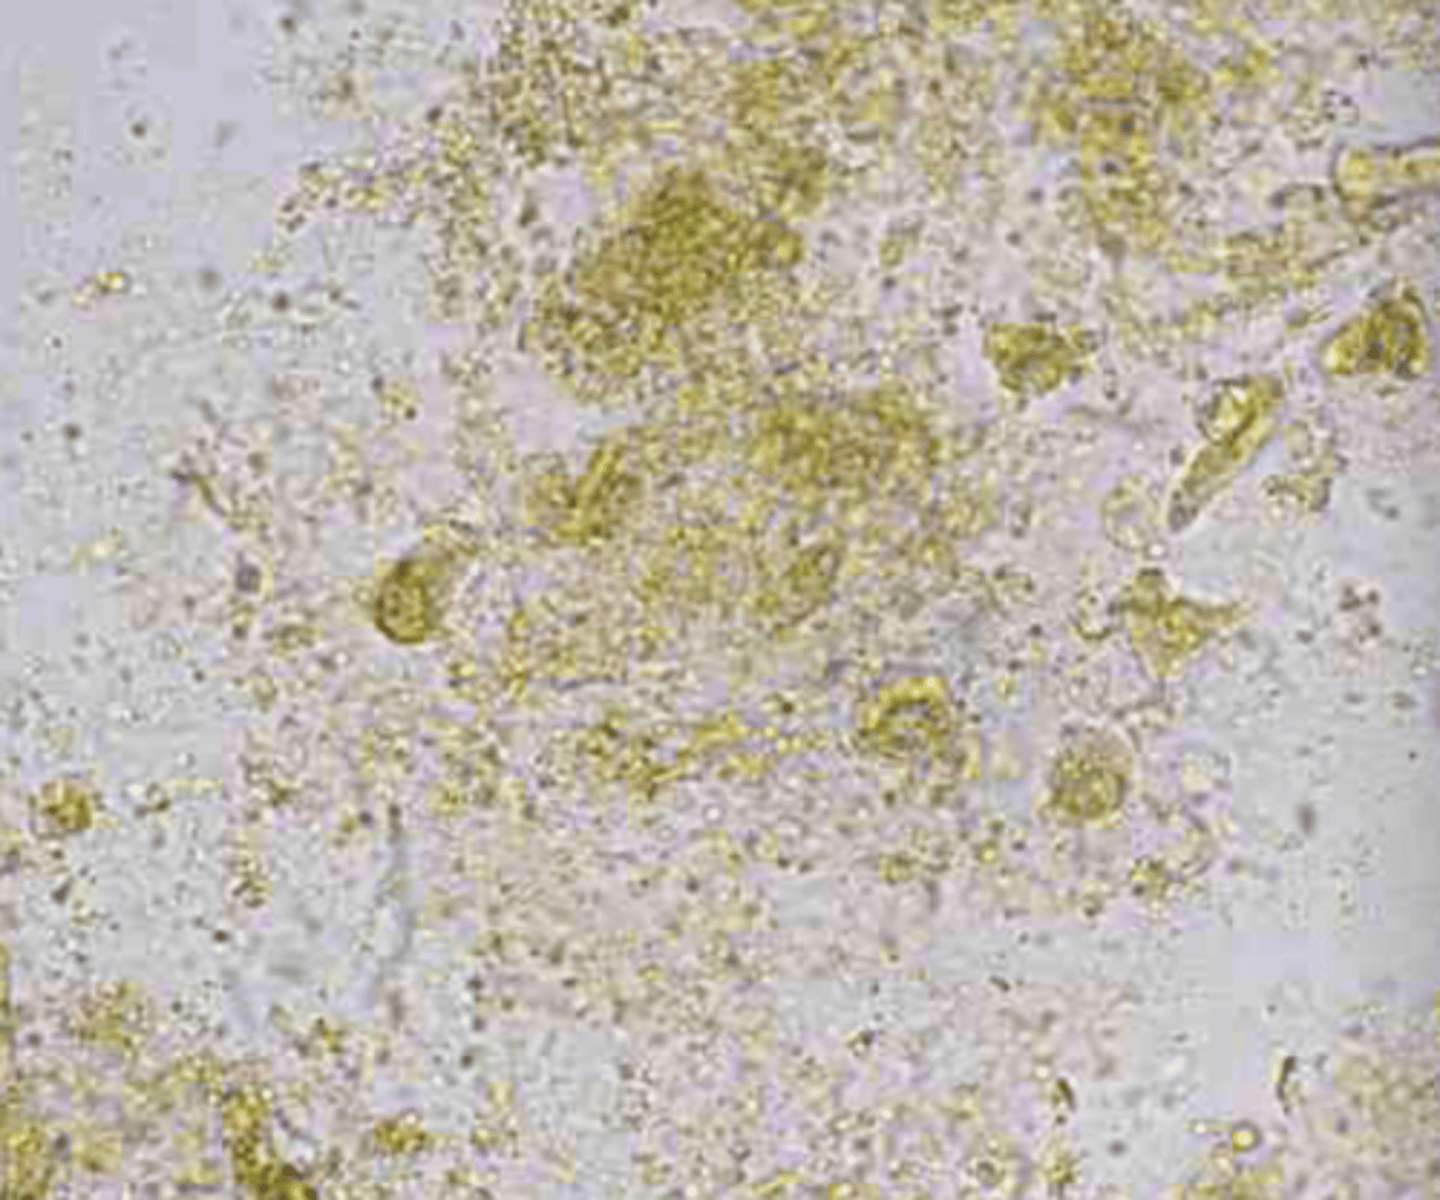

amorphous crystals (debris)

urine

not clinically significant (shows sample age)